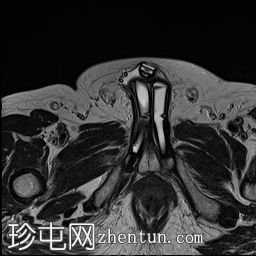

轴位

T2加权像

5.jpg

MRI显示可充气式阴茎假体位于体内。

假体柱体对称地位于阴茎海绵体内,并沿其走行方向完全扩张。

未见海绵体破裂或假体柱体断裂的迹象。

泵储液囊位于阴囊内,位置正常。

阴囊壁皮下可见轻度水肿,但无明显积液,可能为反应性水肿。

储液囊位于右侧腹股沟管前方的皮下脂肪内,对右侧腹直肌施加轻微的向上压迫,周围有少量积液。这些发现最符合术后改变。